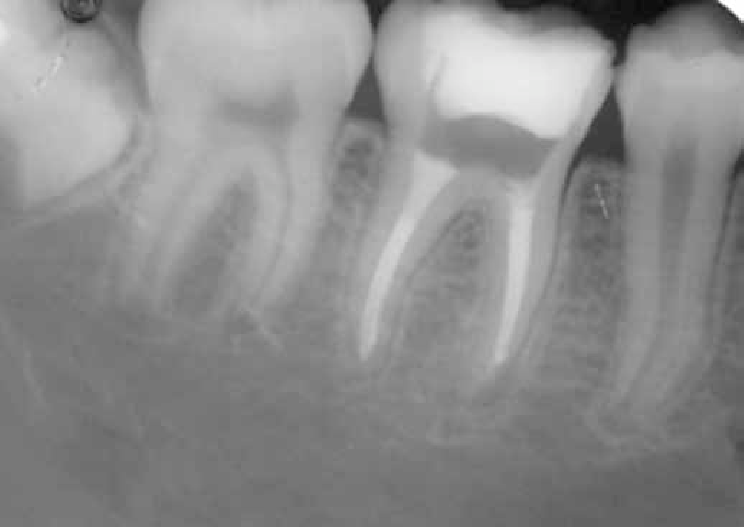

– Não redução da lesão ou surgimento da mesma no ápice do dente;

presença de lesão inflamatória

Após isso, são feitos exames radiográficos (em alguns casos é necessário uma tomografia do dente para ver exatamente onde está o problema) e, a partir disso, um correto planejamento.